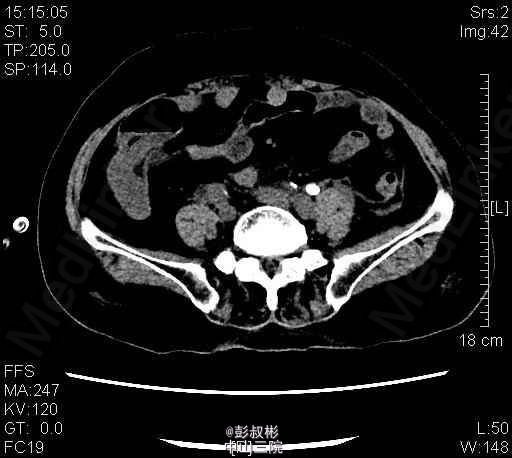

1、患者,女 80岁 2、主诉:左侧腰痛伴发热2天。 3、病史:患者于2天前无明显诱因突发左侧腰痛伴发热,畏寒,最高体温40.1℃,经急诊入院。患者曾于1年前被诊断为“双肾多发结石”,行“左侧经皮肾镜碎石取石术”后好转出院。 4、入院查体:左肾区叩击痛(+),左侧肋脊点、肋腰点压痛(+)。 5、辅助检查:KUB检查示:考虑左输尿管上段结石。B超提示:左肾积脓。胸部正位片:1、双肺纹理增粗,双下胸膜增厚。2、心影增大,主动脉硬化。 6、诊疗过程:患者于入院当晚突发高热、伴寒战、畏寒,最高体温40℃,伴恶心、呕吐,立即予抗感染等治疗。经有效治疗后患者体温有所下降。 随后患者突发抽搐,仍伴寒战、畏寒、意识模糊,予地塞米松10mg静推,加用凡拉蒙2ml肌注,非那根20mg肌注,冬眠灵12.5mg肌注后,控制仍不佳。遂行床边穿刺、抽脓。术后症状有所缓解。术后继续抗感染,患者体温恢复正常,症状明显缓解,无其他不适,遂予出院。